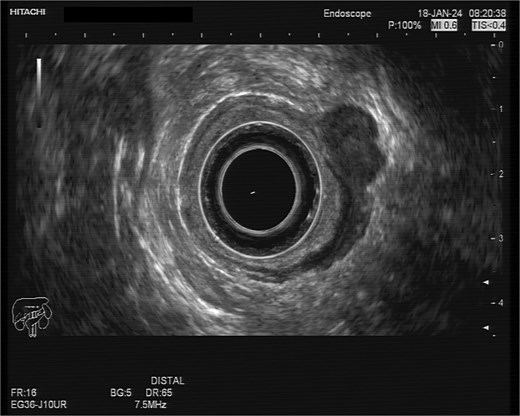

A 75-year-old woman with a past surgical history of serous papillary ovarian carcinoma underwent complete debulking surgery and adjuvant chemotherapy treatment 2 years prior to her current presentation. During follow-up, increased FDG uptake along with a 1.2-cm mass was seen on a PET-CT on the serosal surface of the recto-sigmoid junction (Fig. 1). An attempt was made to evaluate the lesion using trans-rectal sonography. Radial sonographic view showed a 12 mm, hypoechoic, well-defined lesion located at the serosal surface of the recto-sigmoid junction (Fig. 2). After reverting to a linear view, the lesion was sampled with fine-needle biopsy (Fig. 3) and whitish thick cores were retrieved (Fig. 4). The procedure was uneventful and no adverse events were noted. Pathology revealed fragments of high grade serous carcinoma of tubo-ovarian origin. Relying on the histological information gained from the biopsy, it was known that the lesion although not obvious to the eye during surgery, had to be found and resected. The surgical procedure was challenging with multiple adhesions, which made it difficult to locate the lesion. Based on the valuable preoperative knowledge, the patient was able to have a complete debulking of the tumor mass.

Radial sonographic view of the malignant lesion at the 2 o'clock position.